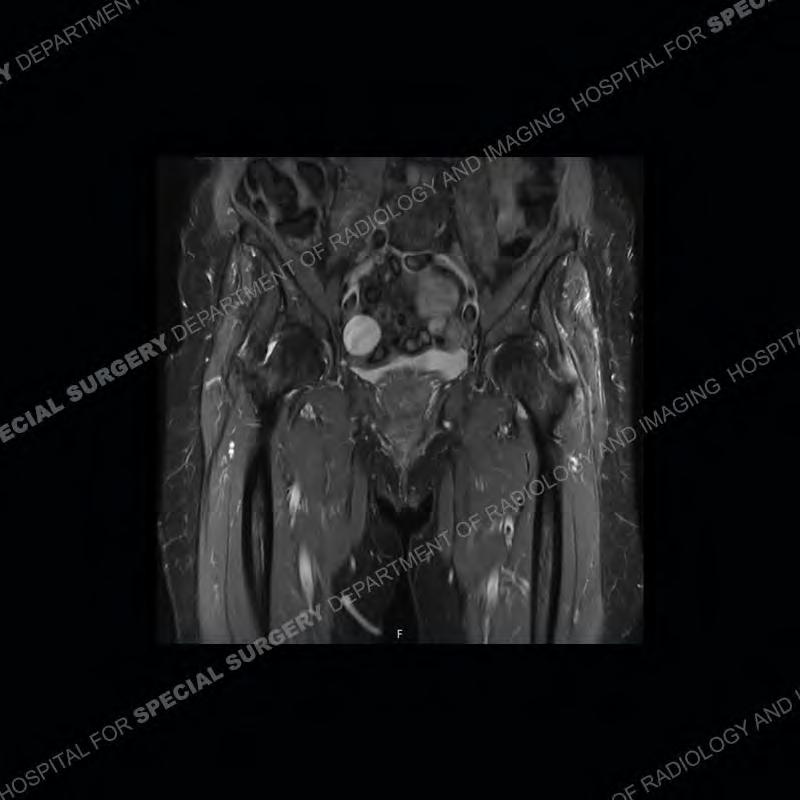

The radiograph is not particularly contributory in this case. The MRI demonstrates markedly abnormal architecture of the gluteus minimus and anterolateral band of the gluteus medius. Portions of the tendons are high signal, portions are highly attenuated, and portions are disrupted. A large, complex fluid collection is present in the adjacent soft tissue.

Diagnosis: Gluteal Tendinosis and Disruption with Complex Trochanteric Bursal Collection

Not as much of a diagnostic dilemma as many of the other cases shown but just a nice example of the pathology seen of the gluteal tendons and a cause of trochanteric pain. Although, frequently thought of in isolation, trochanteric bursitis or bursal thickening is much more commonly a reactive change to underlying pathology of the subjacent gluteal tendons. The gluteus medius is divided into a posterior band and an anterolateral band. Tendinosis and partial tearing very commonly will involve the gluteus minimus and especially the more posterior fibers and then propagate into the anterior lateral band of the gluteus medius. Involvement of the posterior band of the medius is much less common and engenders a marked degree of functional impairment.

The bursae about the greater trochanter can be a little bit confusing especially given the terminology. Trochanteric bursitis is implied to mean the subgluteus maximus bursa which is present deep to the maximus and just lateral/superficial to the trochanter. That is the bursa involved in this case. In this case the complexity of the bursa relates to the tendon tearing with inflammatory change and probably hemorrhage accounting for the complexity. Two other, less frequently involved bursa are also present. The subgluteus medius and subgluteus minimus bursa are found just deep to the named tendons. Although pathology does frequently follow the previously described pattern it is possible to have isolated pathology to either the medius or minimus.